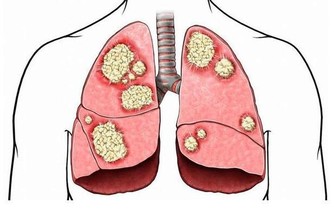

隨著年齡的增長,老年人各器官的生理功能逐漸衰退,許多疾病(特別是慢性病)的發生率上升,老人每天同時服用3-6種藥物不等,殊不知,即便是老年人常用的藥物,尤其是多種藥物聯用,也存在不小的潛在風險。今天就說一說其中10種常用且風險較高的藥物。